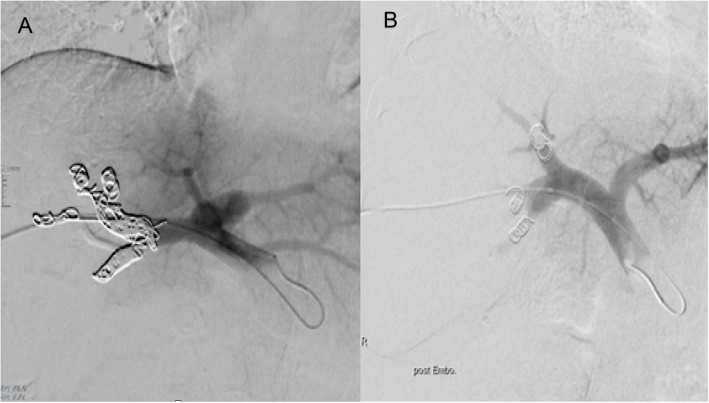

Objective: To assess the efficacy of segmental right portal vein embolization (SRPVE) versus main right portal vein embolization (MRPVE) in preoperative preparation for major hepatectomy.

Methods: This retrospective single-center study included 220 consecutive patients who underwent portal vein embolization (PVE) before (extended) right hemihepatectomy between January 2014 and June 2021. Seventy-one patients underwent selective segmental embolization (SRPVE) and 149 patients underwent MRPVE. Volumetric analysis was conducted before PVE and before surgery. Key endpoints included evaluation of future liver remnant (FLR) hypertrophy, intraoperative complexity, and postoperative complications, technical success, clinical success, complications (Clavien-Dindo and CIRSE classifications), as well as evaluation of different factors which may influence hypertrophy of the FLR.